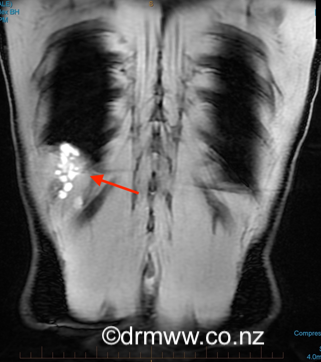

An experienced Endometriosis Specialist usually makes the initial diagnosis by considering the patient’s symptoms along with a thorough history and examination. Because the symptoms can be quite unusual, it’s common for individuals to see various specialists first, such as Cardiothoracic Surgeons, Chest Physicians, or Physiotherapists, before arriving at a diagnosis. Often, many investigations and imaging tests might not show any abnormalities. Chest X-rays and CT scans are commonly done to rule out more common conditions that could explain the symptoms. To confirm the diagnosis more accurately, an MRI performed by an experienced Radiologist is recommended. The best images tend to be captured during a woman’s menstrual period. If the endometriosis lesions are large enough, they can appear as bright white spots (see image 5 & 6).

Image 5 & 6 Posterior diaphragmatic endometriosis seen on MRI as white spots